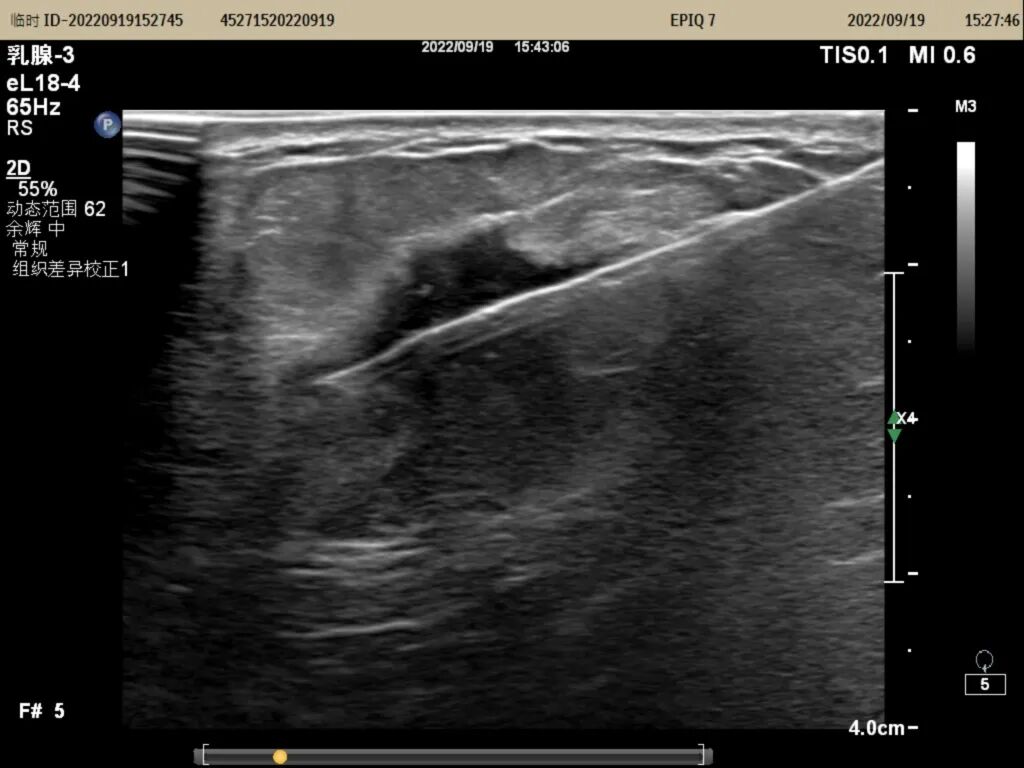

▲右侧乳腺肿物大小约23mm×19mm×21mm,BI-RADS分类:5类

▲实时穿刺图像